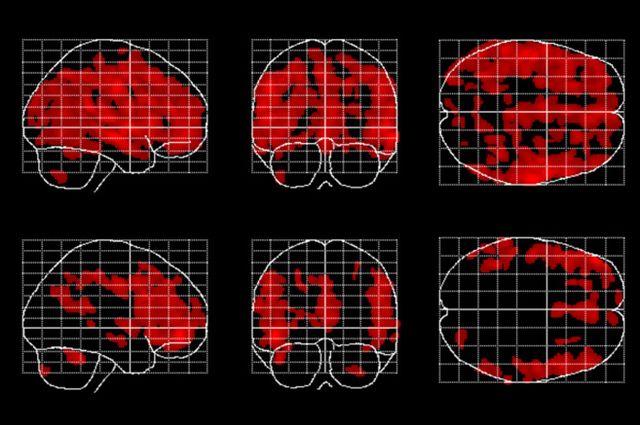

Las áreas del cerebro afectadas por el envejecimiento (en rojo) son menos extensas en las personas que meditan (las de la fila inferior). Imagen: Eileen Luders. Fuente: UCLA.

Los científicos estudiaron específicamente la relación entre la edad y la materia gris. Compararon 50 personas que habían meditado durante años con 50 que no lo habían hecho. Las personas de ambos grupos mostraban pérdida de materia gris a medida que envejecían. Pero entre los que meditaban, el volumen de materia gris no disminuía tanto como entre los que no lo hacían. El artículo aparece en la última edición en línea de la revista Frontiers in Psychology.

"Esperábamos efectos más bien pequeños, localizados en algunas de las regiones que habían sido previamente relacionadas con la meditación", señala. En lugar de eso, lo que de hecho observamos fue un efecto generalizado que abarcaba todo el cerebro."